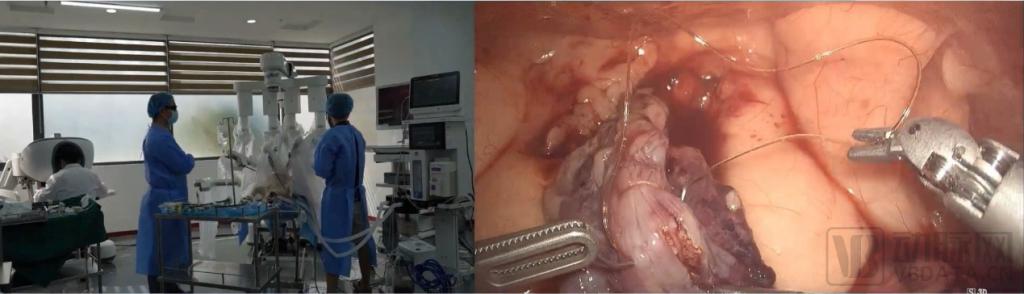

近日该赛道再获新进展,敏捷医疗科技(苏州)有限公司(以下简称 " 敏捷医疗 ")自主研发的 Agibot 腔镜手术机器人自 6 月启动临床前研究以来,已先后开展肾脏切除术、膀胱修补缝合术、膀胱切除术、前列腺根治术等泌尿外科典型术式的动物实验。

图 1 Agibot 腔镜手术机器人开展膀胱修补缝合术

图 2、图 3 Agibot 腔镜手术机器人开展前列腺根治术

据悉,动物实验由苏州大学附属第一医院泌尿外科专家主刀,手术过程顺利,各项操作按预期完成。充分验证了该产品可在腹腔及盆腔狭小空间内处进行分离、止血、结扎、缝合等精细操作,开展全泌尿外科系统术式的能力。并通过循序渐进地开展临床前研究验证和迭代产品功能,为敏捷医疗 Agibot 腔镜手术机器人系统进入注册临床阶段奠定基础。